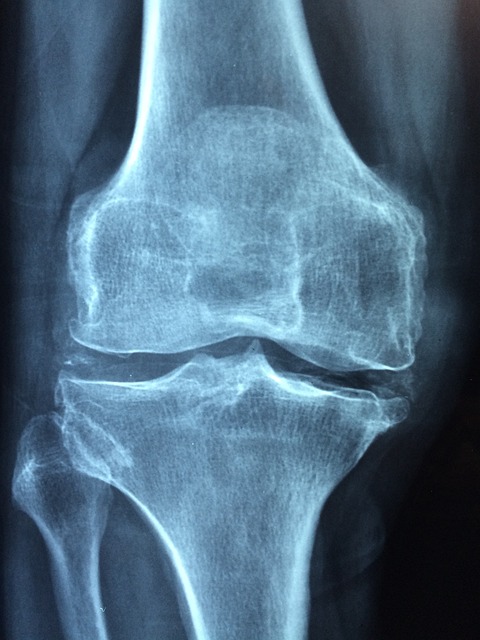

- 관절 통증 감소: 콘드로이친 효능으로 퇴행성 관절염 환자에게서 관절 통증을 줄이는 데 도움 됨이 있습니다. 이는 콘드로이친이 연골의 마모를 방지하고 염증을 줄이는 역할을 하기 때문입니다.

- 연골 보호 및 재생: 콘드로이친은 연골 세포의 생성을 촉진하고, 기존 연골을 보호하는 데 중요한 역할을 합니다. 이는 특히 나이가 들면서 발생하는 연골 손상을 예방하는 데 유용합니다.

- 염증 감소: 연구에 따르면 콘드로이친은 관절 내 염증을 감소시키는 데 효과적입니다. 이는 장기적으로 관절 건강을 유지하는 데 도움이 됩니다.

- 관절 유연성 향상: 콘드로이친 효능으로 정기적인 콘드로이친 복용은 관절의 유연성을 개선하고, 일상 활동의 질을 높이는 데 기여합니다.

여러 연구에서 콘드로이친의 효능이 입증되었습니다. 예를 들어, 골관절염 환자를 대상으로 한 연구에서 콘드로이친이 관절 통증을 감소시키고, 연골 손상을 방지하는 효과가 있는 것으로 나타났습니다. 이러한 연구들은 콘드로이친의 장기적 사용이 안전하고 효과적임을 시사합니다.